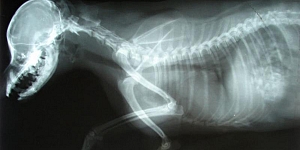

Ikaross, veterinārā klīnika

Veterinārārsts Vetārsts Veterinārā klīnika Veterinārā palīdzība Veterinārie pakalpojumi Veterinārija Dzīvnieku ārstēšana Veterinārā klīnika Bolderāja Veterinārārsts Bolderāja Vetārsts Bolderāja Veterinārija Bolderāja Suņu čipošana Kaķu čipošana Mikročipošana Mikročips Dzīvnieku vakcinācija Vakcinācija